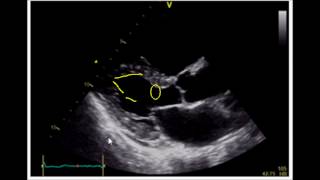

Estimating Ejection Fraction with Point of Care Echo

Shared 9 years ago

409K views